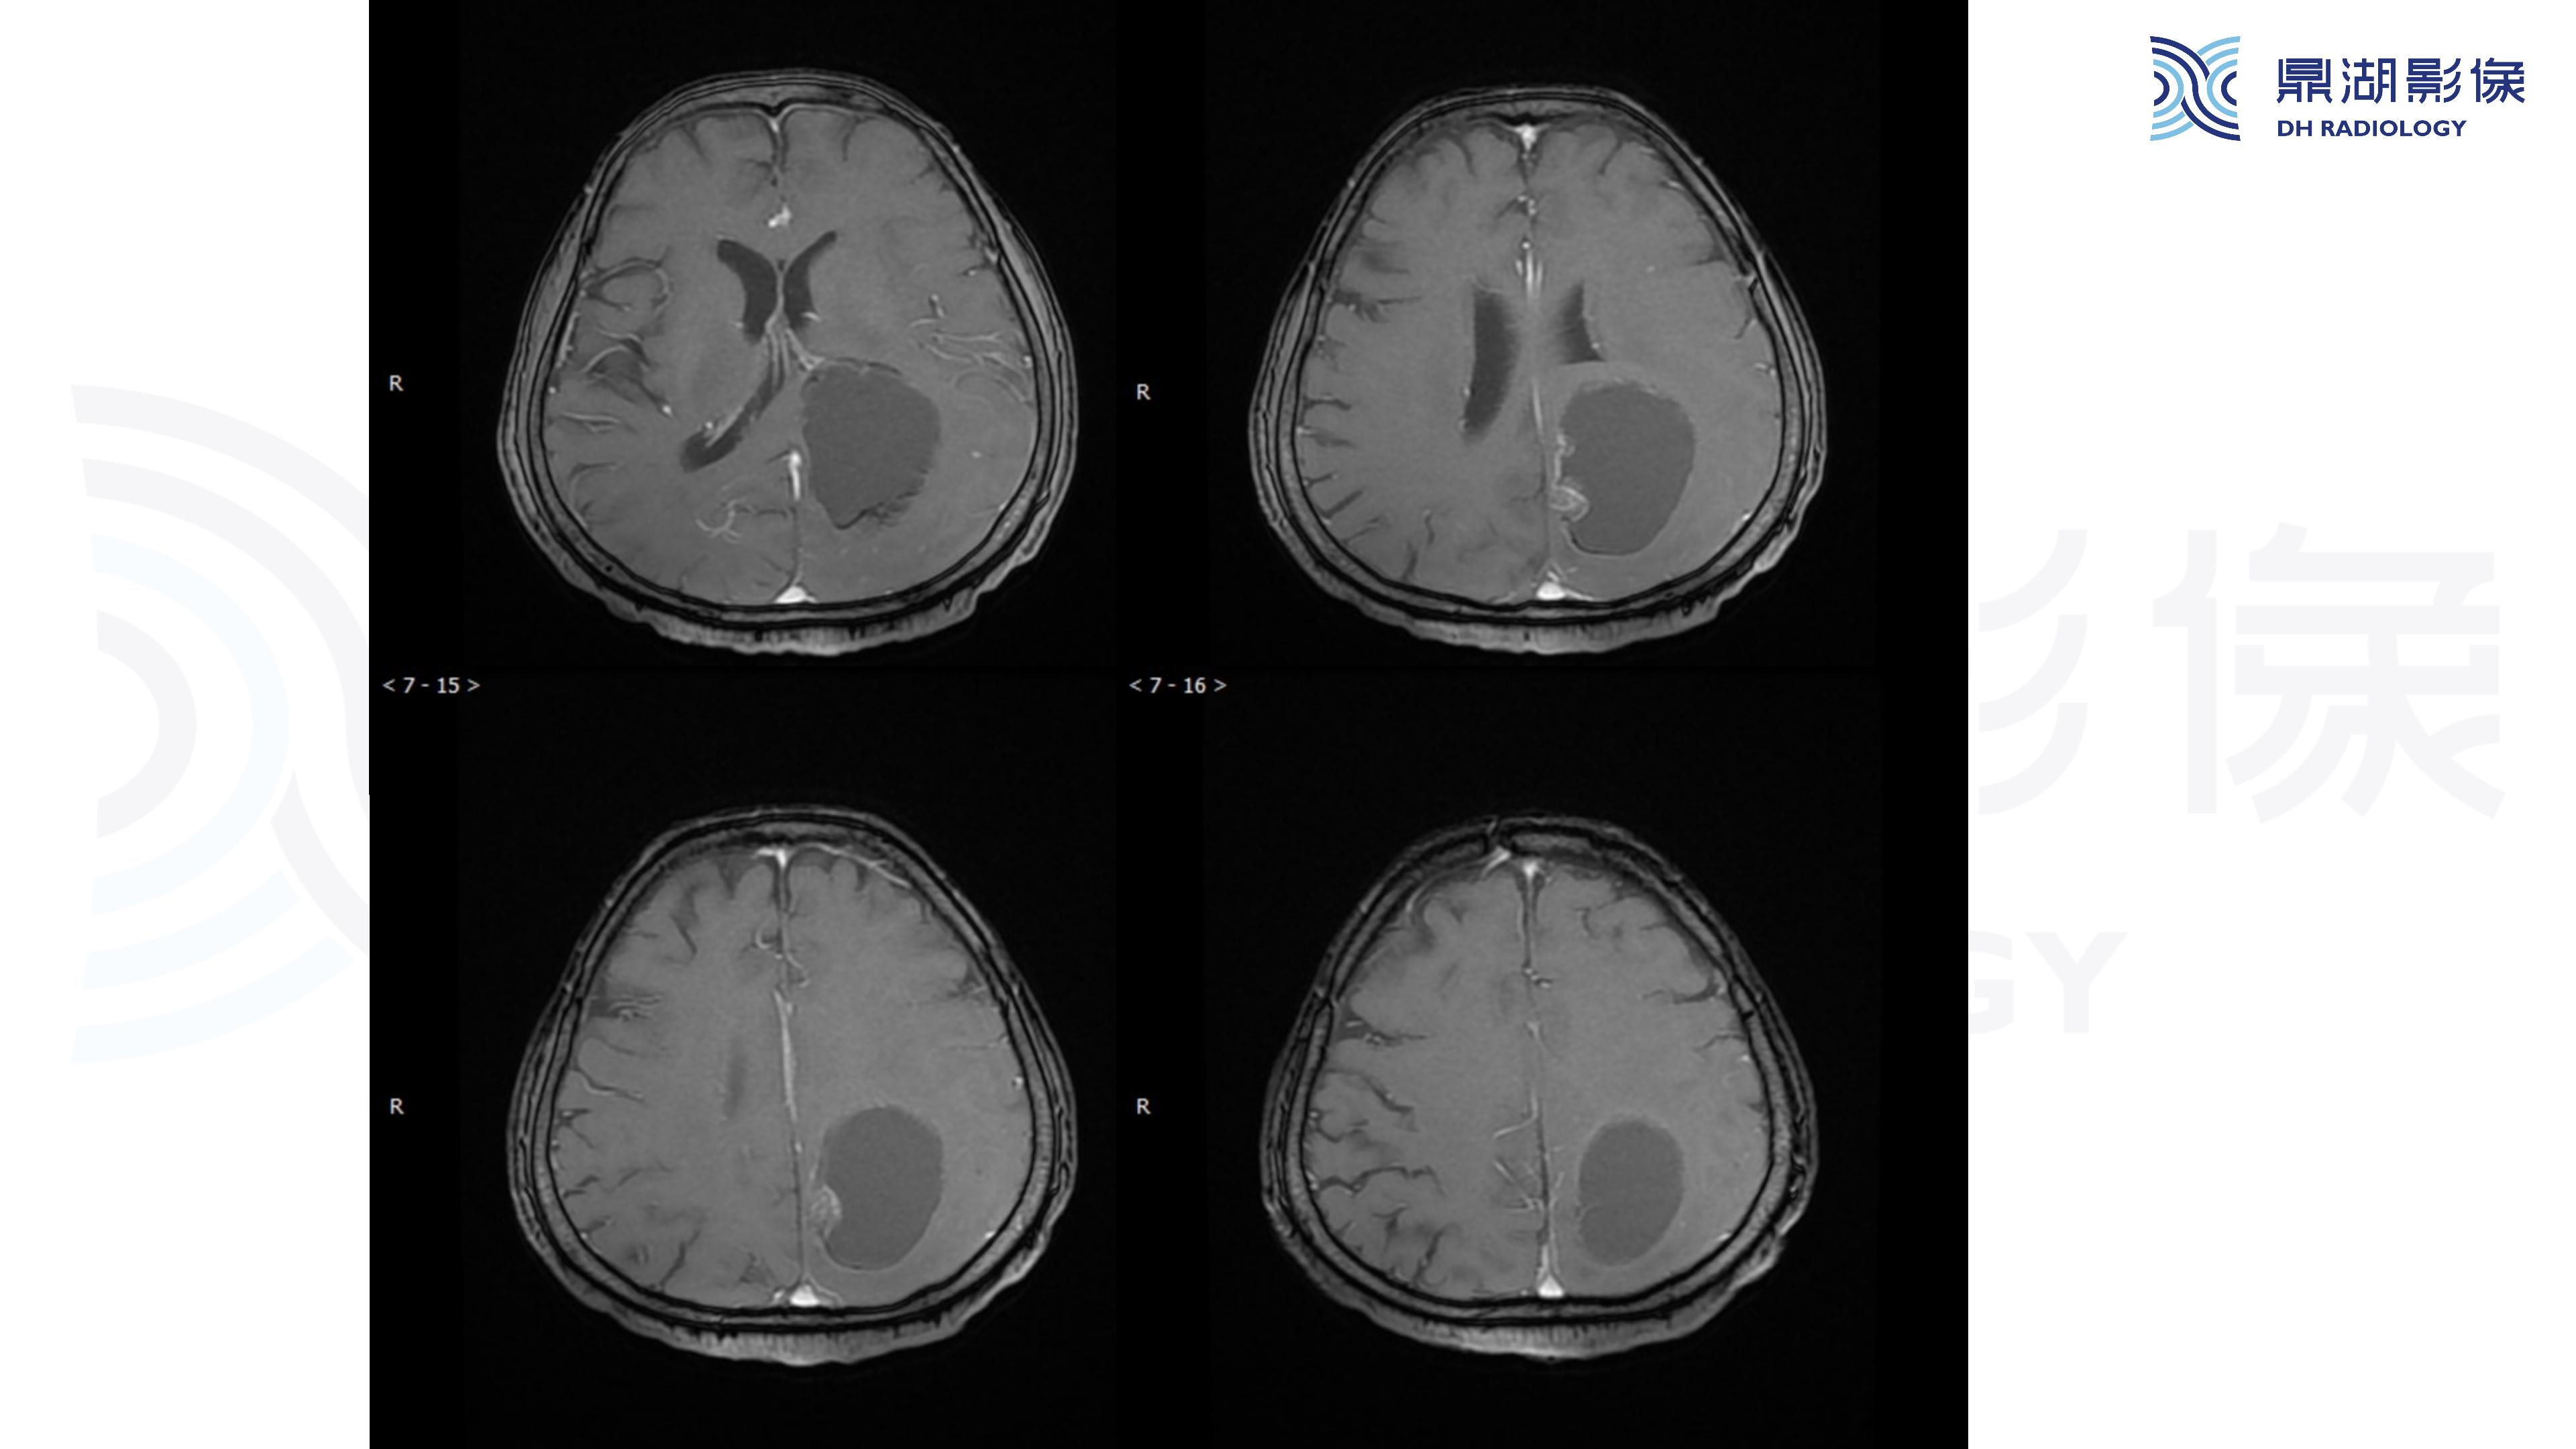

幕上毛细胞型星形细胞瘤(WHO Ⅰ级)